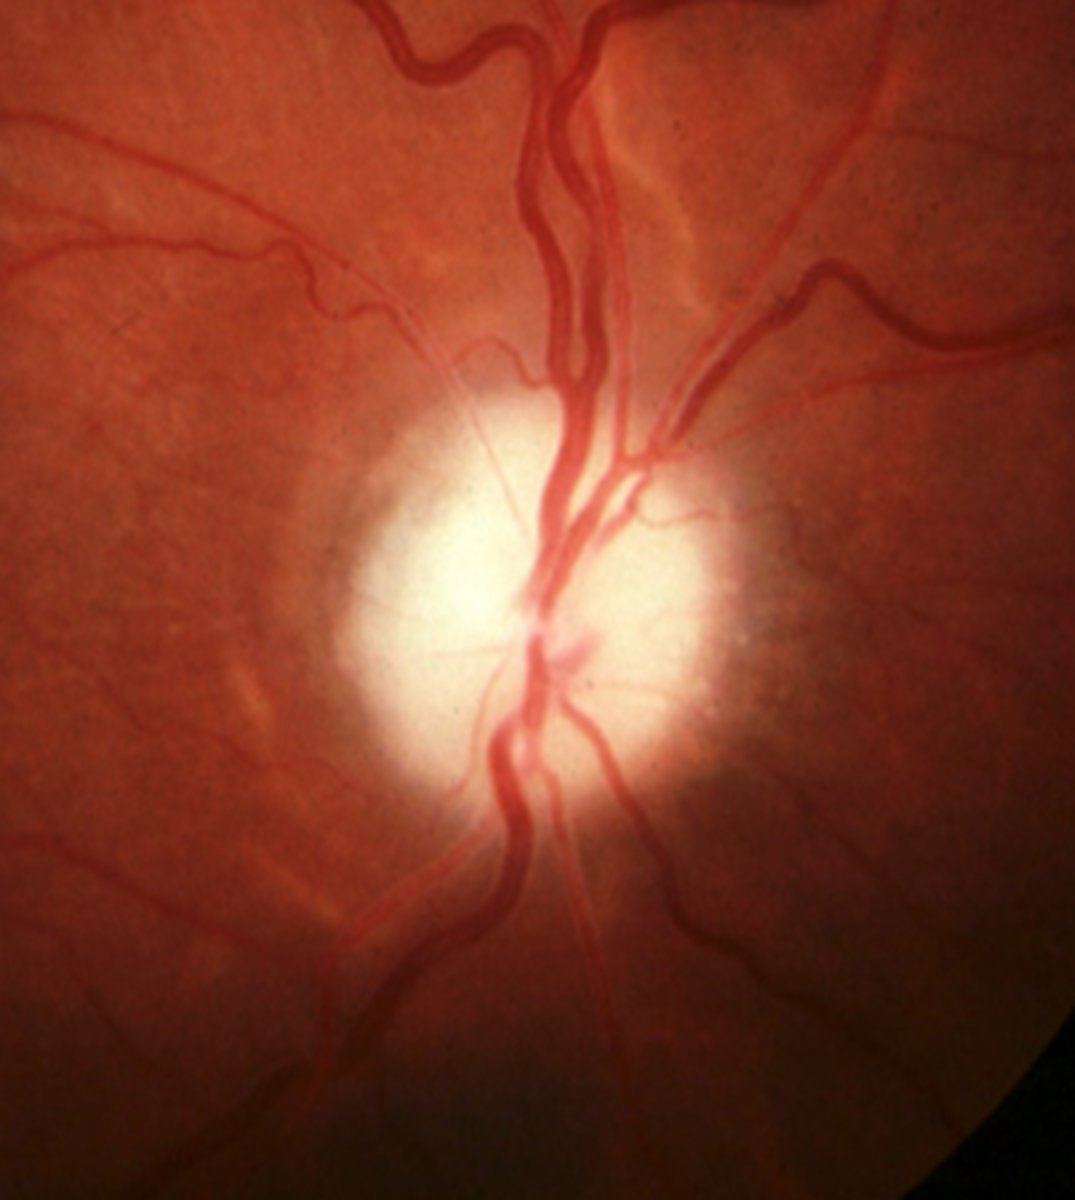

What cause of ascending optic atrophy is shown here?

chronic atrophic papilledema